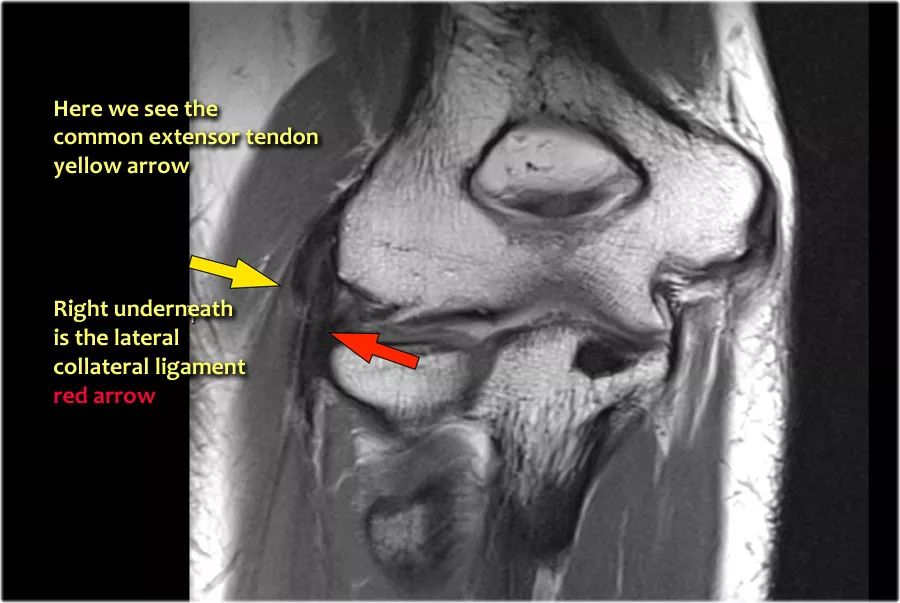

当您寻找桡侧副韧带时,首先要尝试识别常见的伸肌腱,因为在它下面你会发现桡侧副韧带(黄色箭头)。

当你向后走时,你会看到LUCL--侧面尺侧副韧带,它在桡骨头后面扫过(白色箭头)。环形韧带通常难以与RCL区分开,但有时可以在矢状MR-关节造影上识别。